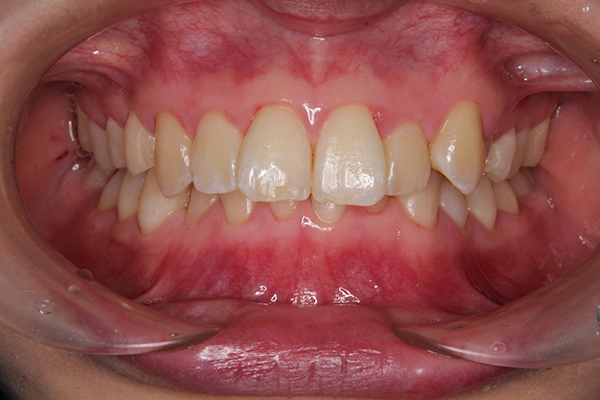

IPRで、歯に隙間ができています!

普段はマウスピースをしているので

この隙間が目立ったりすることはないので

ご安心ください^^